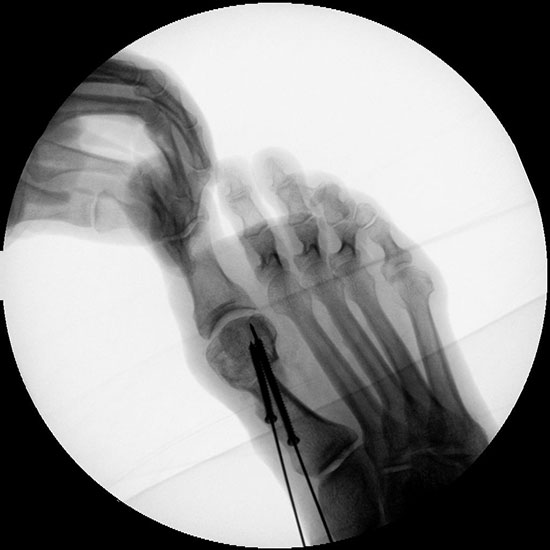

Bei entsprechender Wahl der Osteotomieebene kann auch bei minimalinvasiver Chevron-Osteotomie eine deutliche Plantarisierung des Metatarsalekopfes erreicht werden.

Abbildung 32